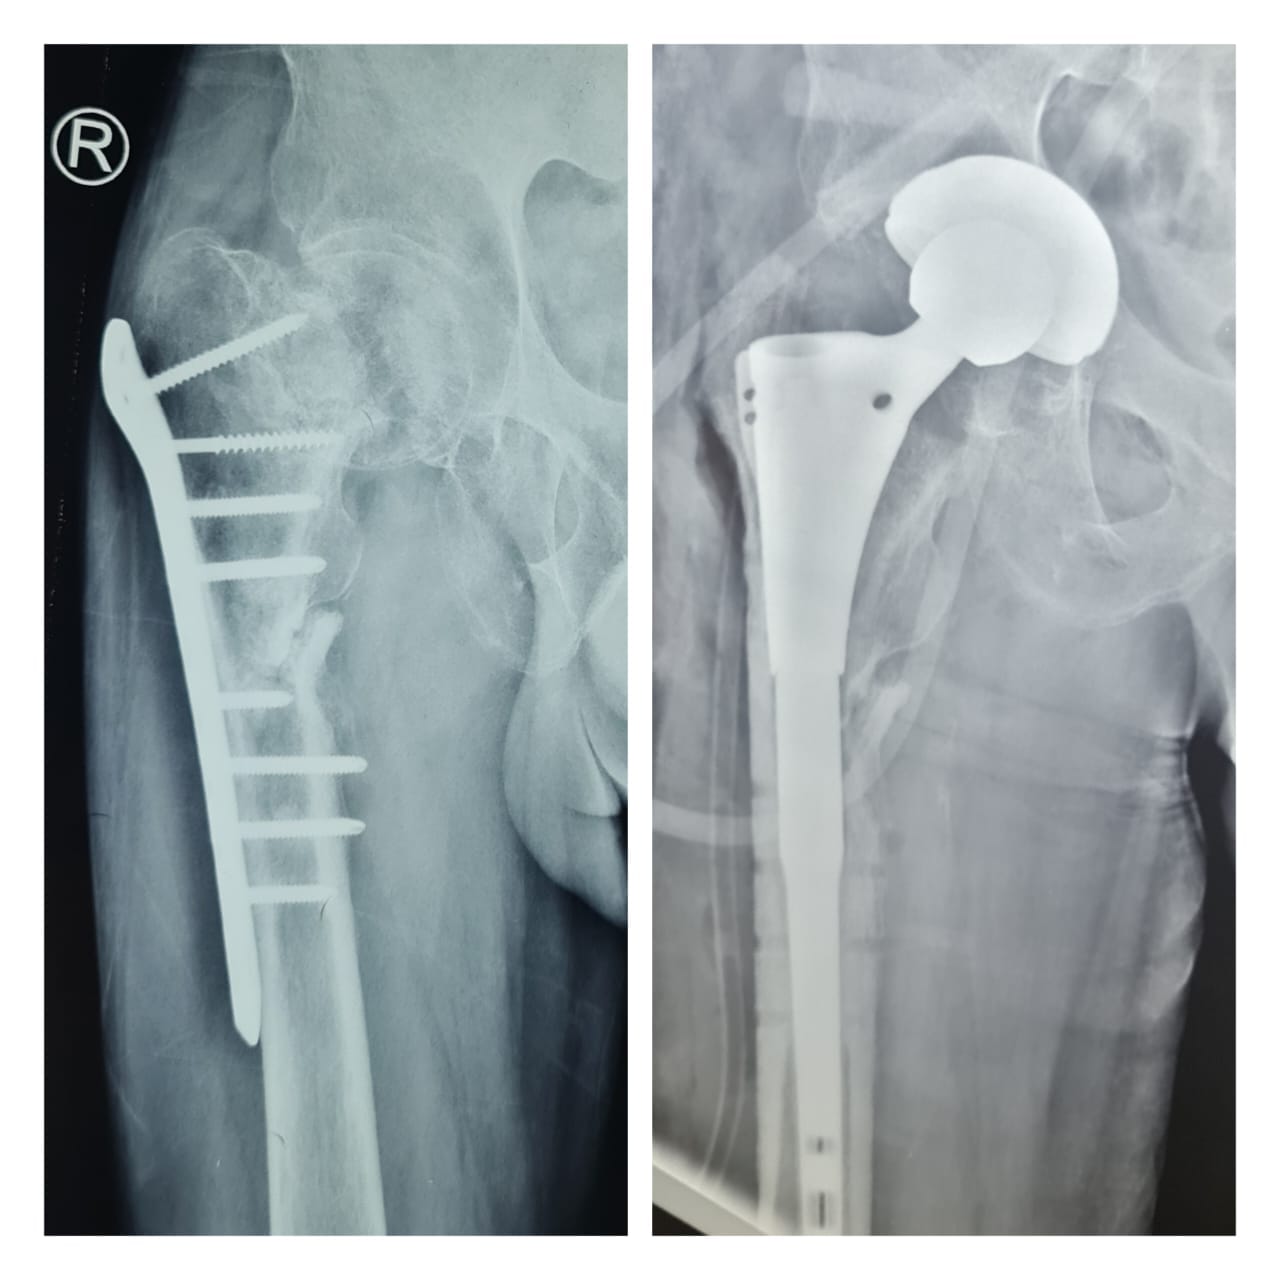

فريق طبي جراحي في مستشفى ابن سينا يجري عملية نوعية و معقدة لتبديل مفصل الورك .

اجرى فريق طبي جراحي في مركز ابن سينا التخصصي لجراحة العظام والكسور و تبديل المفاصل عملية تبديل مفصل ورك معقد...